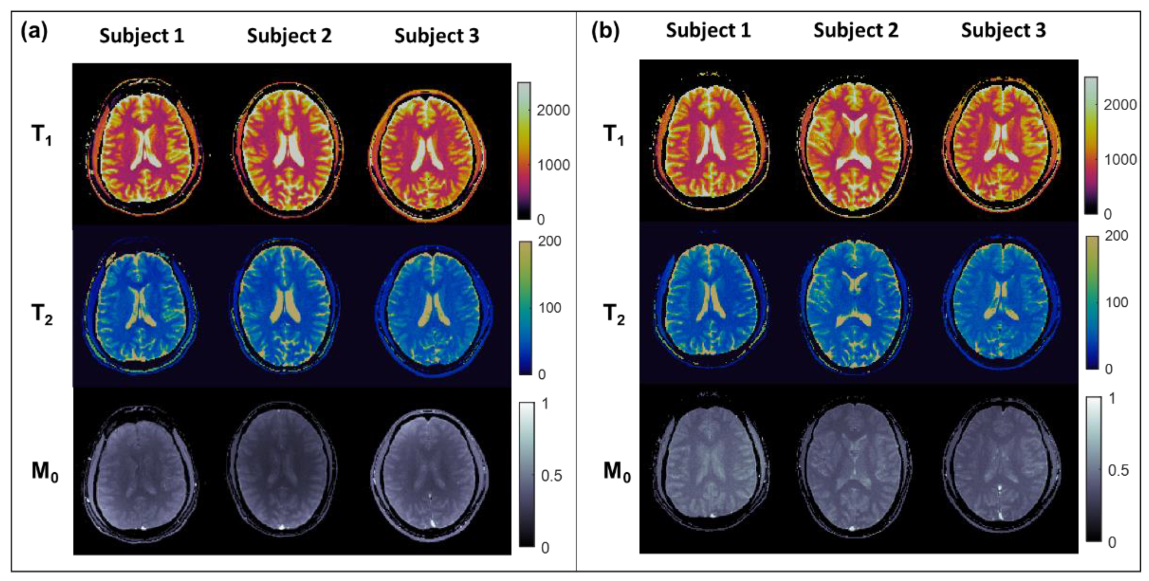

3.2. In Vivo Experiments